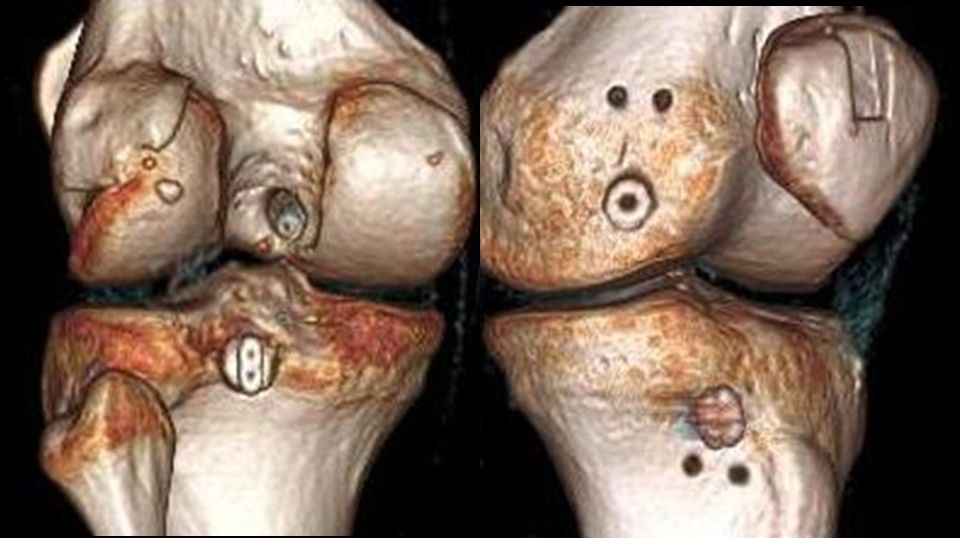

The Indication for operative treatment is based on the amount of posterior translation (borderline according to literature 8 mm) and the additional peripheral instability, which leads to increased posteromedial or posterolateral rotational instability. The indication goes along with the degree of increased rotatory instability and malalignment (Fig 3).

Fig 3 - Radilogical Documentation of Chronic PCL Instability